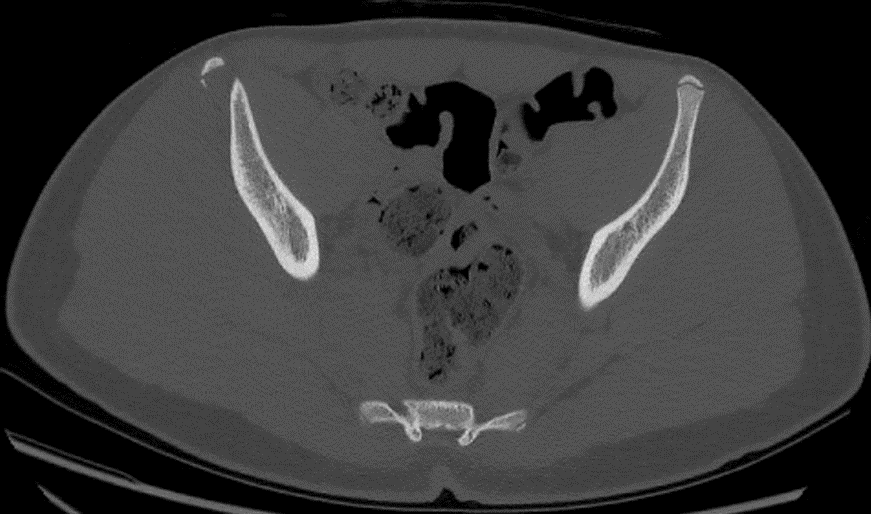

Standard pelvic radiography revealed a displaced bony fragment at the right AIIS. CT scan confirmed the avulsion fracture without intra-articular involvement or adjacent soft tissue injury.

Figure 2. CT scan initial axial slice: EIAI avulsion.